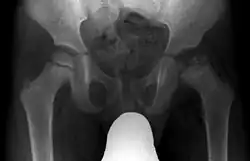

X-rays of the hip may suggest and/or verify the diagnosis. X-rays usually demonstrate a flattened, and later fragmented, femoral head. A bone scan or MRI may be useful in making the diagnosis in those cases where X-rays are inconclusive. Usually, plain radiographic changes are delayed six weeks or more from clinical onset, so bone scintigraphy and MRI are done for early diagnosis. MRI results are more accurate, i.e. 97–99% against 88–93% in plain radiography. If MRI or bone scans are necessary, a positive diagnosis relies upon patchy areas of vascularity to the capital femoral epiphysis (the developing femoral head).[11]